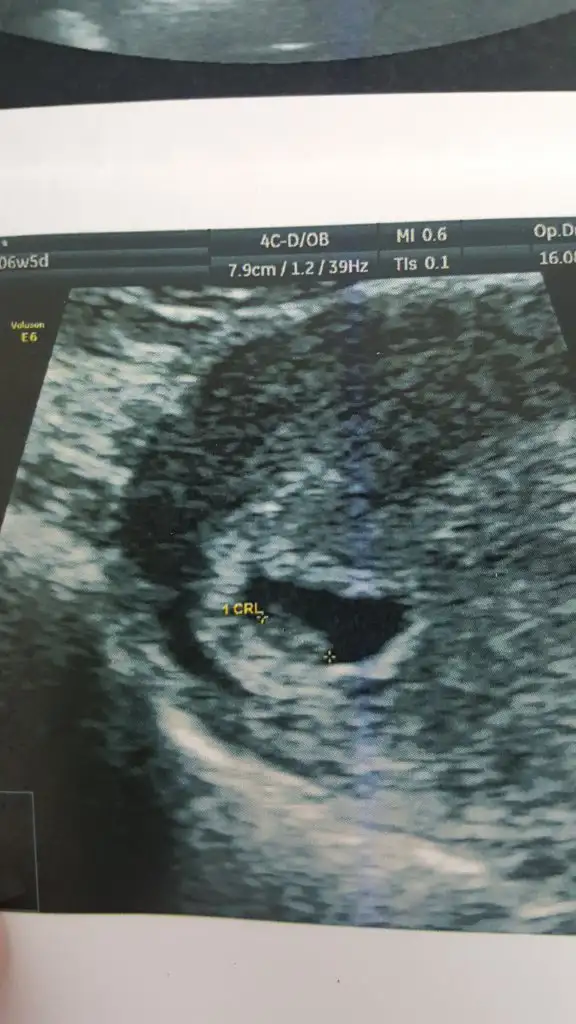

Kızlar ben kontrolden geldim karından baktılar hem bebeği hem kalp atışını gördüler ama doktor çok emin olamadı kalp atışından bide vajinal bakmak istedi vajinal bakınca daha net bir şekilde kalp atışı var dedi çok şükür cihazları zayıf olduğundan sanırım biraz görüntü kalitesi bozuk ama yine de atayım yorumlarınıza açığız 🤗😍